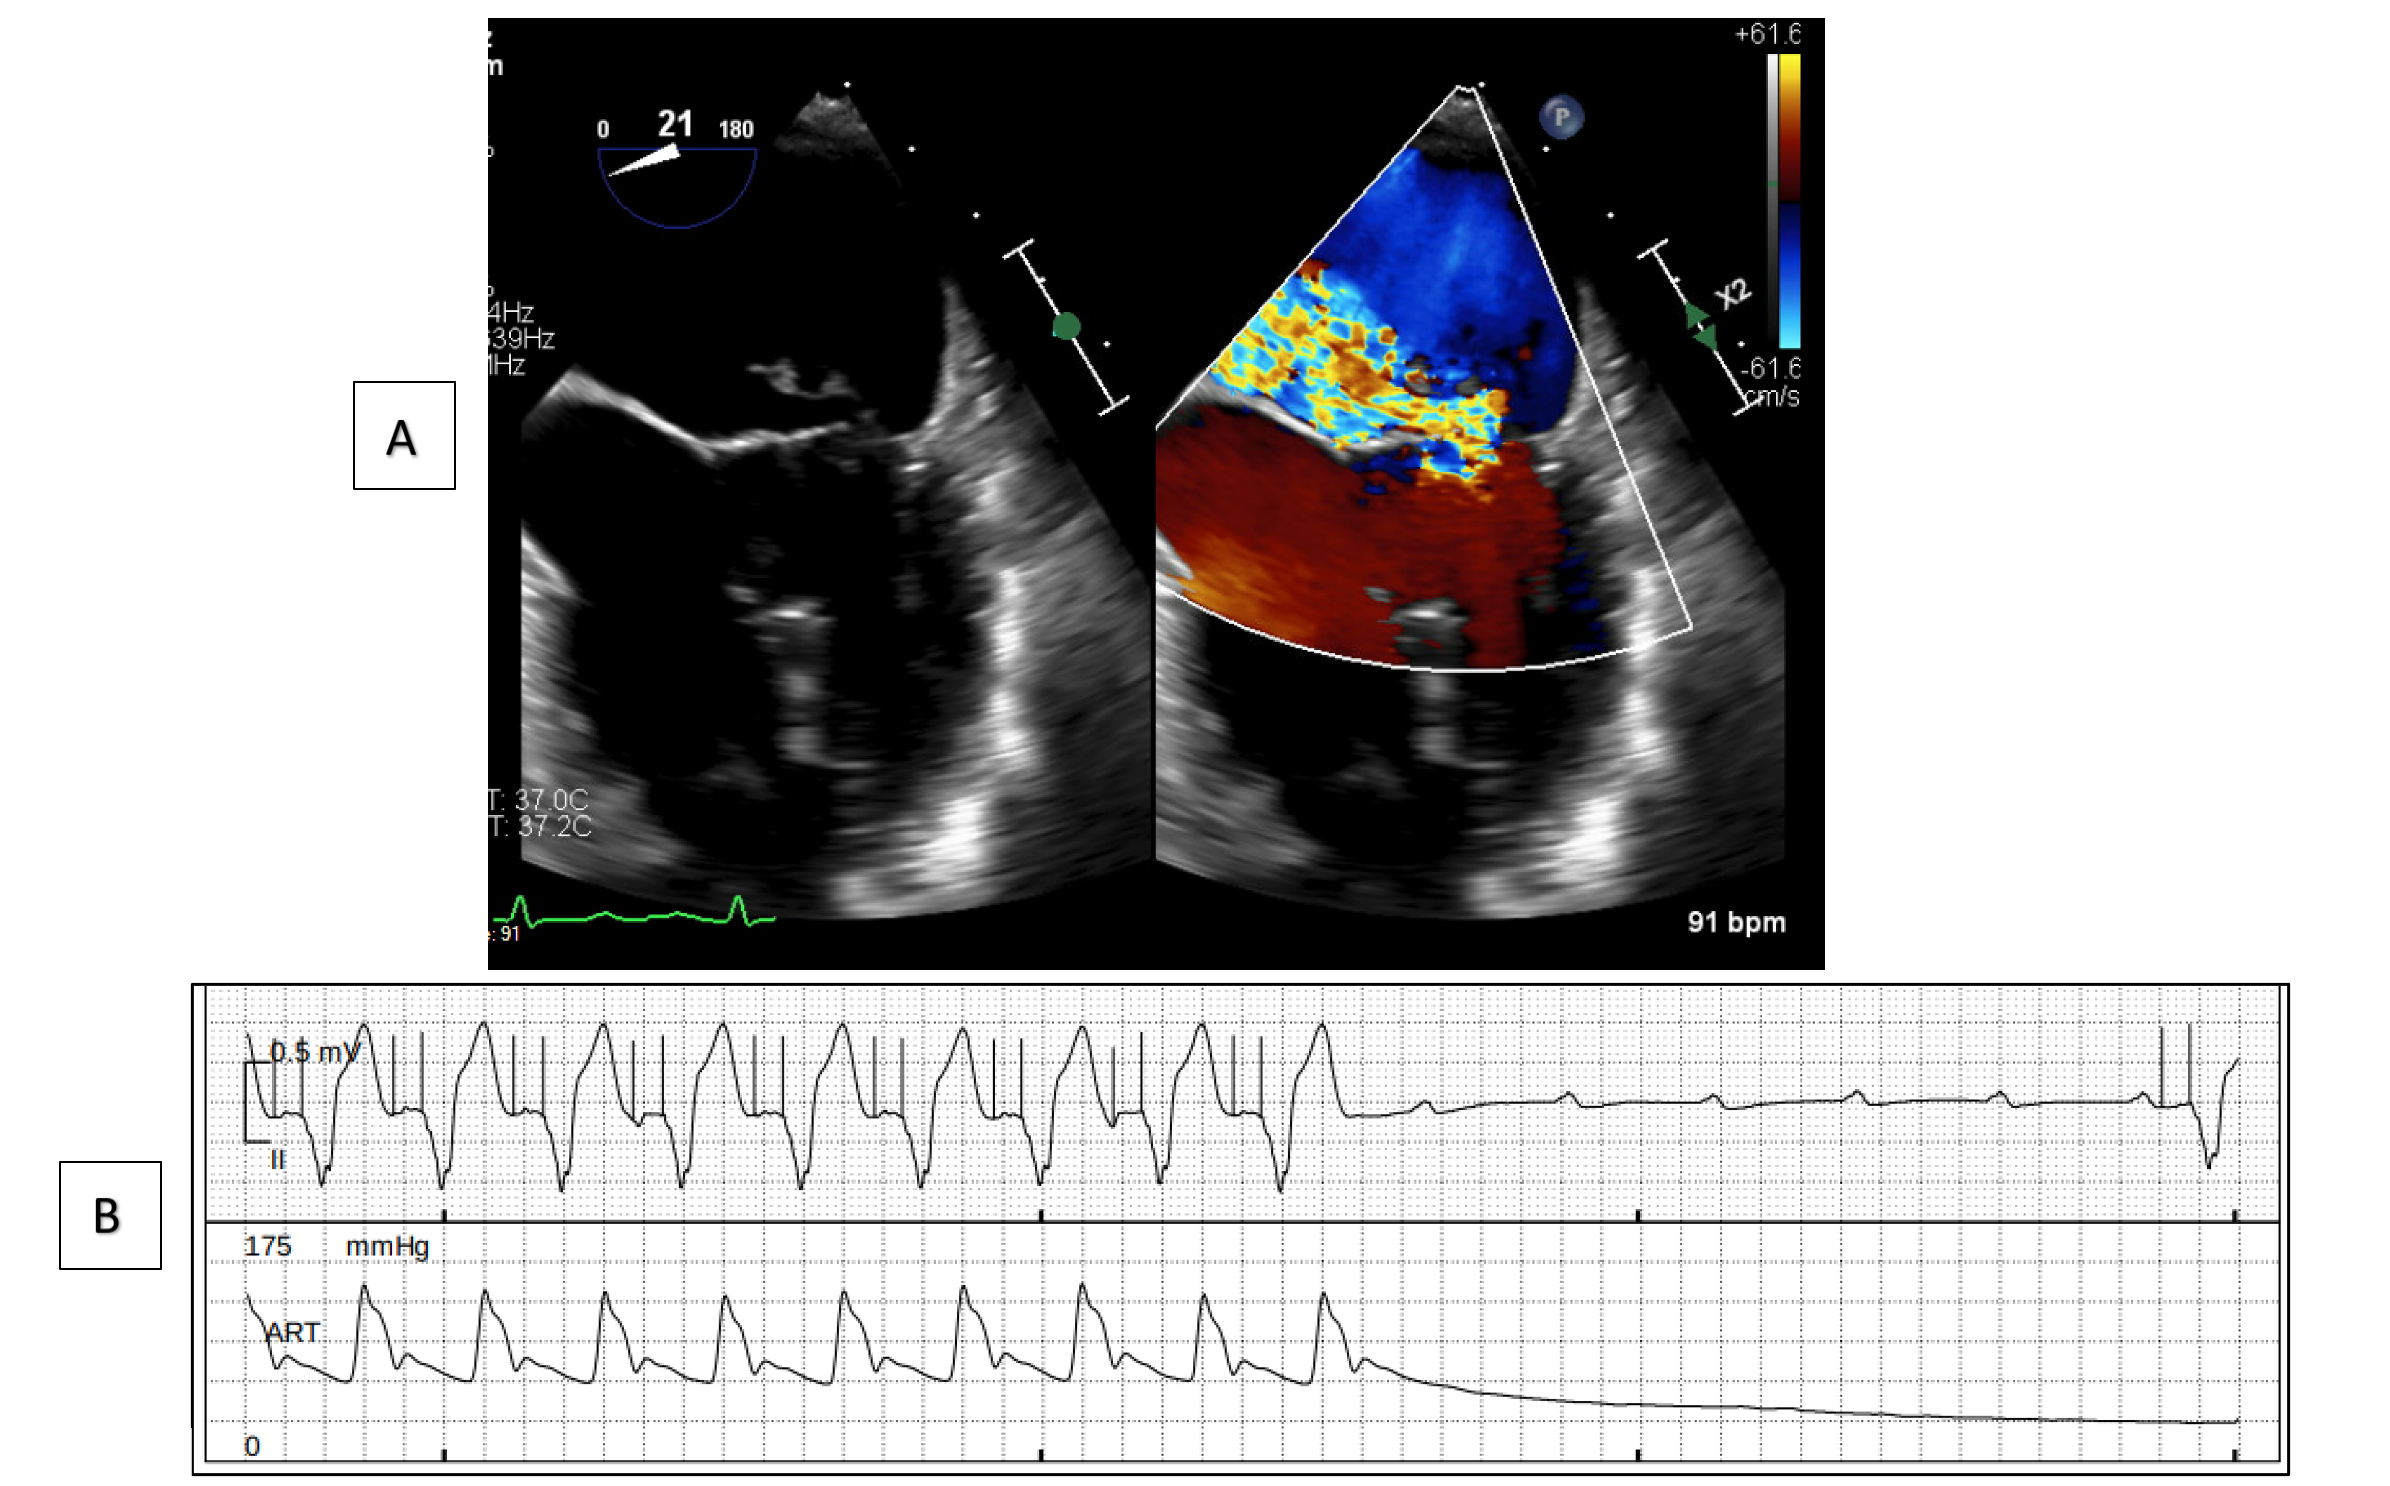

A 77-year-old woman with hypertension presented with acute dyspnea, new-onset atrial fibrillation, and a holosystolic murmur. Transesophageal echocardiography revealed a flail P2 scallop with acute severe MR and preserved ejection fraction. The left ventricular internal diameter was within normal limits but showed concentric hypertrophy. She developed cardiogenic shock with acute kidney and liver injury. Impella CP was initiated to augment forward flow and unload the LV using a target P-7 setting, as intra-aortic balloon pump was deemed insufficient due to its afterload-reducing mechanism. Over 48 hours, end-organ function improved markedly. During support, frequent ventricular ectopy was observed. At mitral valve replacement, septal bruising was noted despite appropriately shallow device positioning (3.2 cm), and intermittent complete heart block required temporary epicardial pacing. A permanent dual-chamber pacemaker was placed the next day due to persistent conduction issues. She recovered well and was discharged home ambulatory.

Although intra-aortic balloon pump remains the most common MCS in acute MR due to ease of use, Impella may provide superior forward flow when LV unloading is needed. While complete heart block is recognized post-mitral surgery, its preoperative onset here implicates device-induced septal injury. The patient’s small, concentrically remodeled LV may have increased septal vulnerability. Though rarely reported, conduction disturbances from axial-flow MCS have been sparsely described and may be underrecognized.